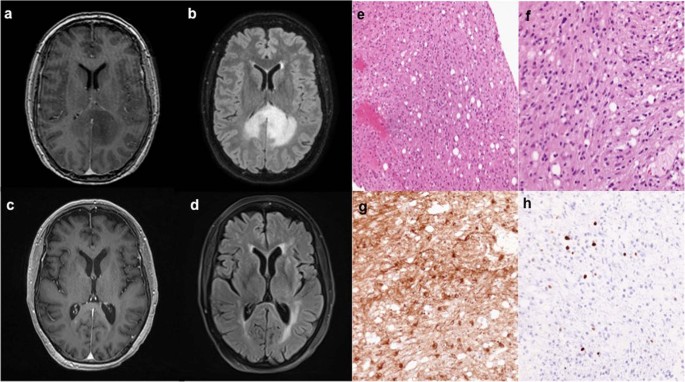

A 65-year-old female presented to an outside institution with several weeks of headaches and acute worsening of progressive numbness in her right lower extremity. Her past medical history was only significant for basal cell carcinoma of the left nasal ala, resected 5 years prior. Her family history was notable for breast cancer of middle-aged onset in her sister, mother, and grandmother but no prior diagnosis of a familial cancer predisposition syndrome. Her symptoms prompted magnetic resonance imaging (MRI) of the brain, which revealed a predominantly non-enhancing right parietal lesion with patchy enhancing foci extending to the splenium of the corpus callosum (Fig. 1a, b). Further imaging with computed tomography (CT) of the chest, abdomen, and pelvis did not reveal a primary systemic tumor to suggest a diagnosis of brain metastasis. She subsequently underwent stereotactic biopsy of her lesion with pathology demonstrating a glial neoplasm, consistent with World Health Organization (WHO) grade II astrocytoma (Fig. 1e–h). The Ki-67 index was 1–3% and immunohistochemical staining for TP53 was positive. Further molecular testing was negative for the EGFR variant III, IDH1 mutation, and MGMT promoter methylation. She was subsequently referred to our institution for further adjuvant treatment, where she underwent adjuvant radiation therapy and temozolomide treatment, as well as use of tumor-treating fields (TTF) with the Optune device (Novocure, Jersey, U.K.). A brain MRI obtained several months after completion of chemoradiation and TTF showed radiographic response with stable small foci of enhancement and drastic reduction in perilesional edema (Fig. 1c, d). Clinically, the patient was stable with moderate cognitive deficits and requirement of mild assistance with activities of daily living.

a Representative axial slices of T1-weighted MRI after contrast administration and (b) T2-weighted FLAIR obtained prior to stereotactic brain biopsy show a predominantly non-enhancing lesion within the deep right parietal lobe with small areas of patchy enhancement that is crossing the corpus callosum with associated edema. Repeat imaging obtained nearly 2 years after biopsy and completion of adjuvant chemoradation demonstrates (c) stable foci of small nodular enhancement on T1-weighted MRI after contrast administration with (d) minimal associated edema on T2-weighted FLAIR. e, f An infiltrating astrocytoma without necrosis or vascular proliferation is seen on hematoxylin & eosin staining. g Immunohistochemistry for GFAP-positive tumor cells is shown and (h) the Ki-67 proliferative index was ~3%.